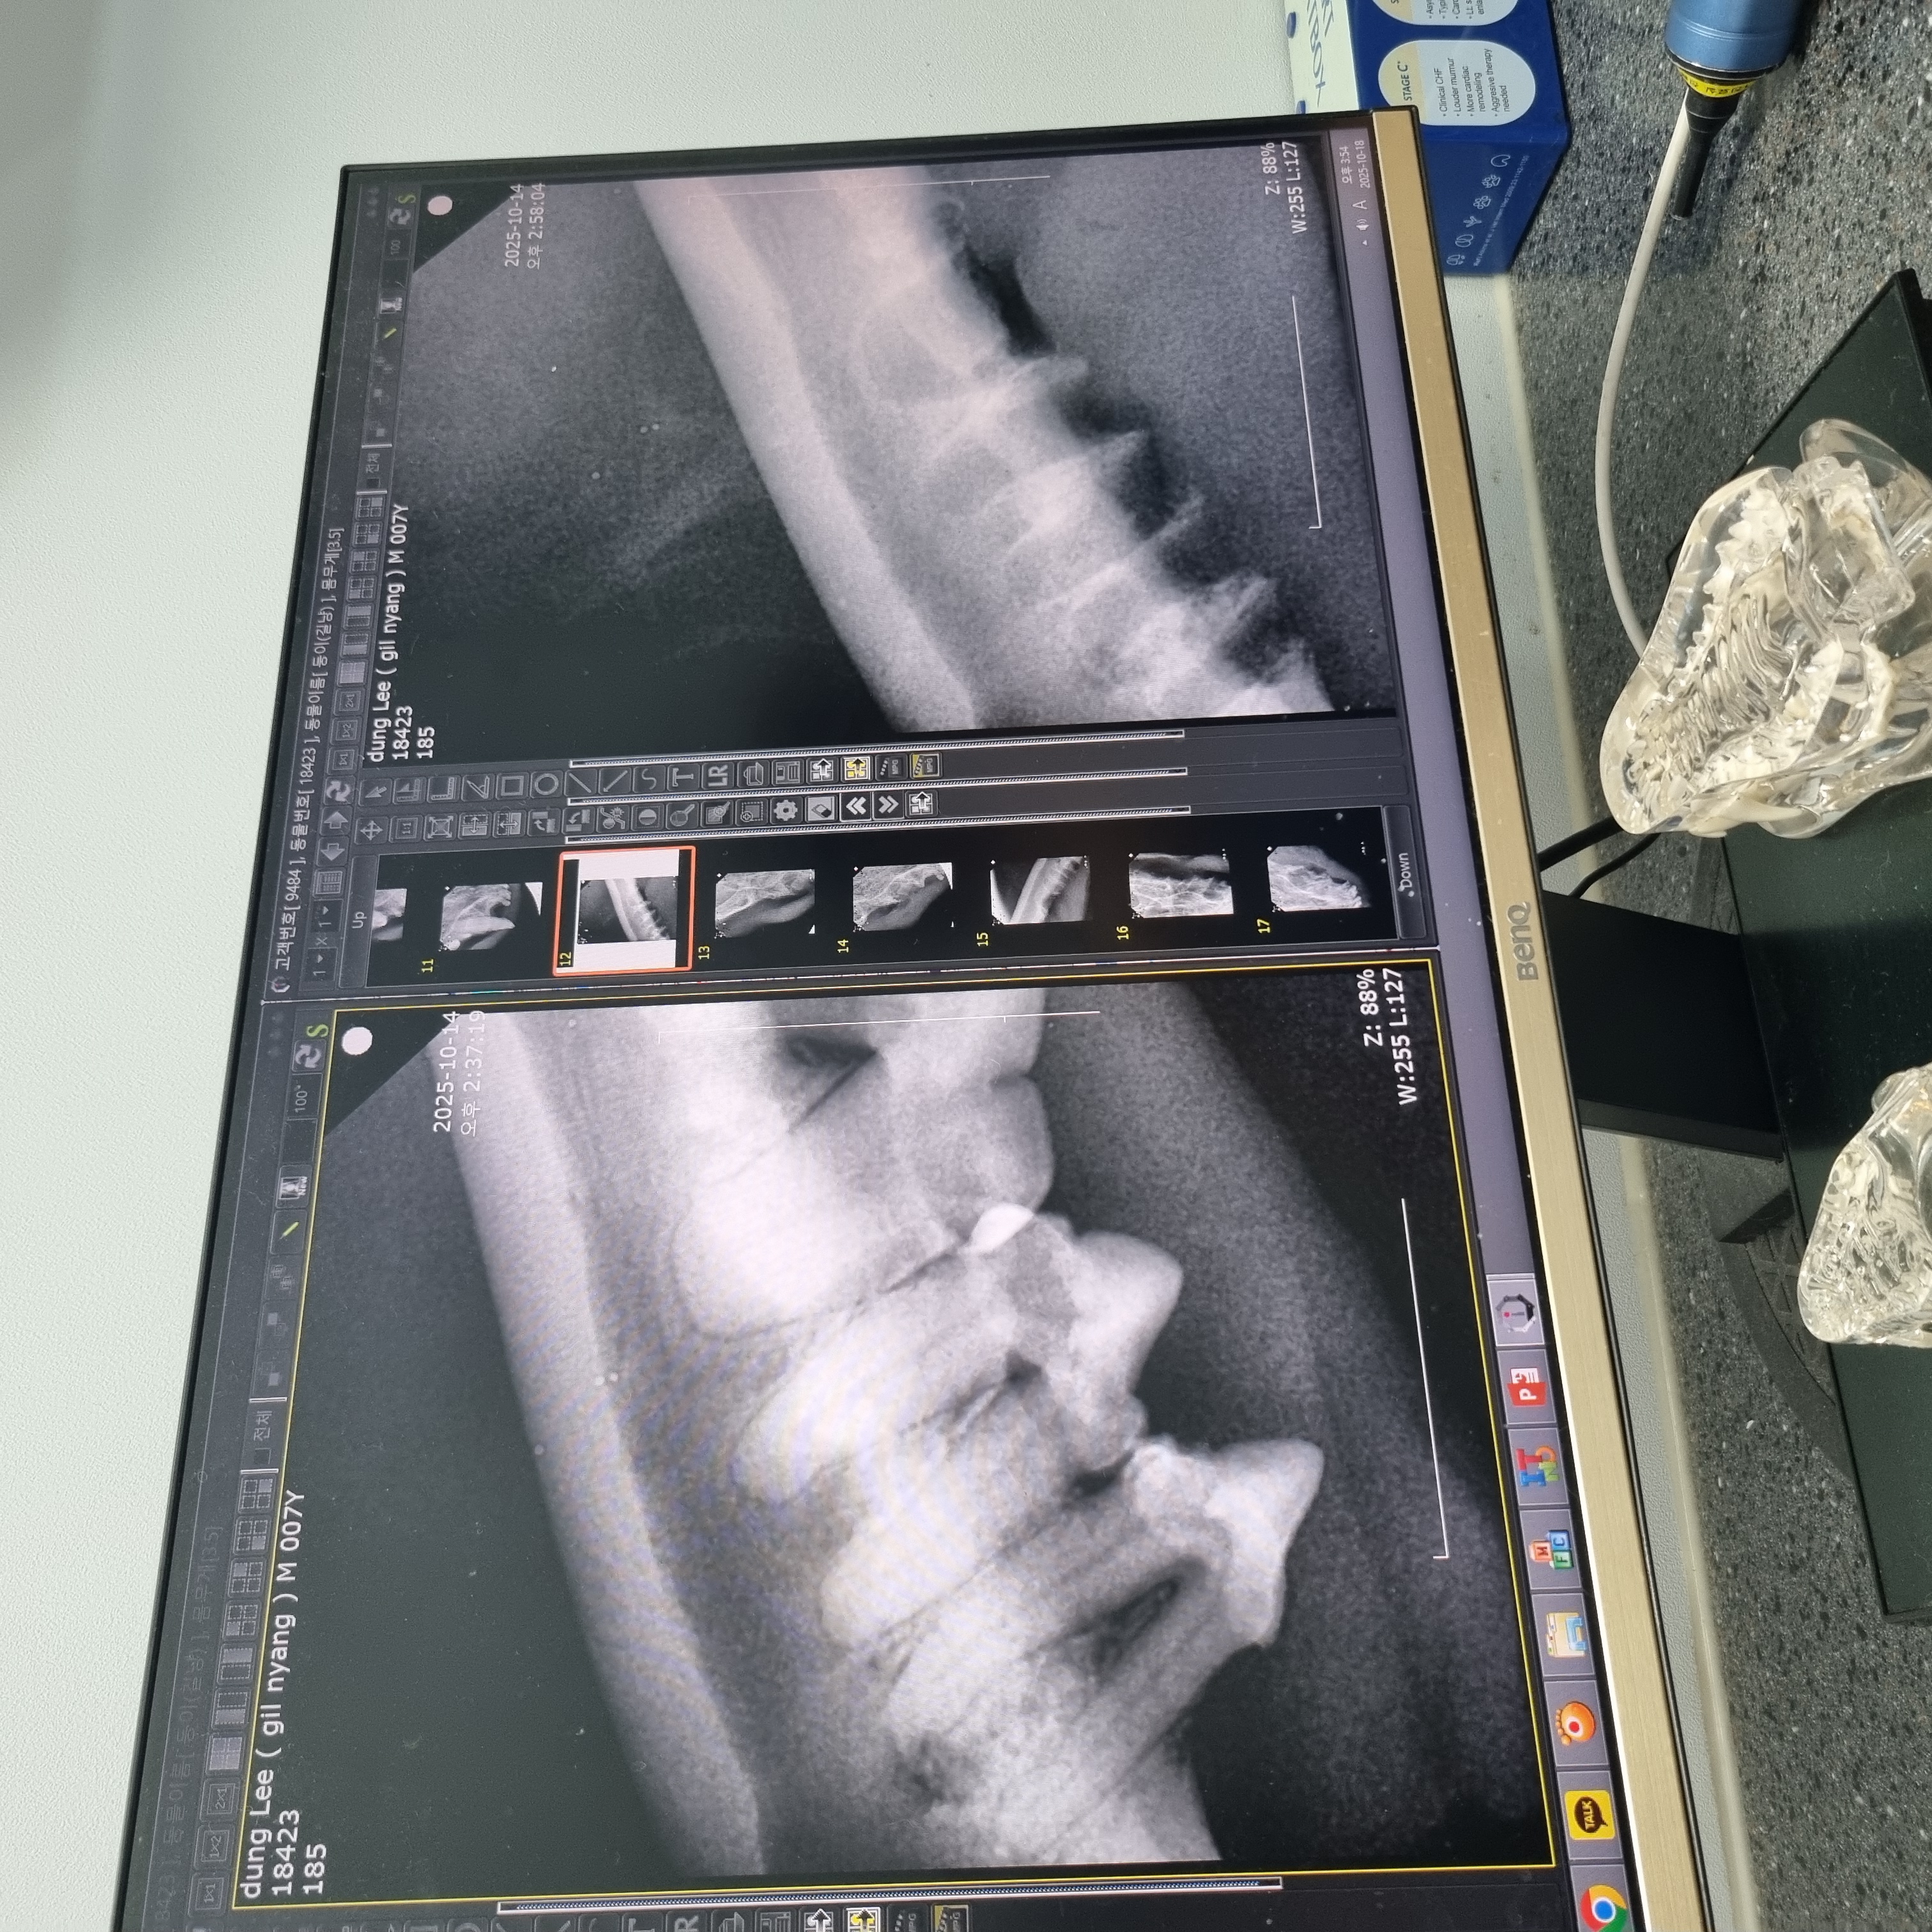

| 치료과정 | 츄르나 파우치를 먹을 때 아주 크게 왕!! 하고 짖는 등 고통을 호소하고 작년보다 최소 2~3킬로는 빠진 모습이라 급히 치료지원신청을 하였고 당일 둥이 구조에도 성공했습니다 둥이는 10월 4일에 구조하게 되었고 이후 병원에 내원하여 정확한 상태를 확인받았습니다. 우리 둥이 마취 후 입 안을 보니 전발치를 해야하는 아주 전형적인 증상이라고 사진을 보여주셨습니다. 둥이의 목구멍 주위에 동그랗고 빨갛게 부은 염증부터 삭아버린 이빨... 얼마나 고통스러웠을지 사진을 보고 마음이 너무 아팠어요. 둥이의 수술을 위해 혈액검사와 키트검사 등을 진행하고 전발치수술을 하게 되었습니다. 수술 이후에는 병원에서 송곳니까지 깨끗하게 전발치한 사진을 치아엑스레이를 찍어 상세하게 보여주셨습니다. 수술을 마친 이후에는 병원에 입원시켜서 수액 처치도 받고 회복에 전념하였습니다. 둥이는 며칠전에 면회때만 해도 좀처럼 기운이 없어 여러 걱정이 많았는데 다행히 어제 면회 때는 기력을 되찾은 모습입니다. 큰 소리로 야옹거리기도 하고 입원실 밖도 돌아다니고 먹고 아주 조금 남은 습식사료까지 싹싹 핥아먹는 모습을 보였습니다. |